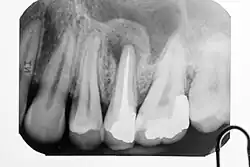

Wenn die primär chronische Form in eine akute Entzündung umschlägt, tritt ein typischer Klopfschmerz auf. Röntgenologisch sind apikale Aufhellungen meist erst nach mehrwöchigem Krankheitsverlauf zu erkennen. Als erstes Anzeichen ist ein erweiterter Periodontalspalt sichtbar. Veränderungen der Knochendichte sind im Röntgenbild erst erkennbar, wenn mindestens 30 % des Mineralgehaltes des Knochens abgebaut sind. Das kann bei einer apikalen Ostitis einige Tage bis Wochen dauern. Bei geringen Beschwerden und unsicherer Aussagekraft des Röntgenbildes ist eine Wiederholungsaufnahme erst nach drei Monaten angebracht.

Differentialdiagnose: apikales Granulom oder radikuläre Zyste; Zustand nach Wurzelbehandlung; Vorwölbung der apikalen Aufhellung in die Kieferhöhle

Die Unterscheidung einer apikalen Periodontitis von einer dentogenen Zyste (radikuläre Zyste) ist nur histologisch möglich. Die ältere Lehrmeinung, dass röntgenologische Aufhellungen über 7 mm Durchmesser eher für eine Zyste sprechen, wurde verworfen. Ebenso, dass ein scharf abgegrenzter Rand im Röntgenbild eher für eine Zyste spricht.